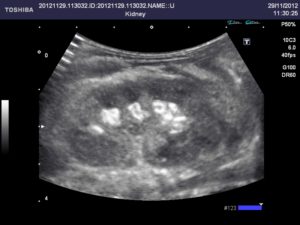

Структура ткани

Структура почечной ткани однородная или гомогенная, без включений. Корково-медуллярная дифференциация (видимость почечных пирамидок) должна быть отчетливо выражена. Почечная лоханка – полость внутри почки – не должна содержать никаких включений.

Изменение структуры почек происходит при различных болезнях. Наличие образований внутри почечной лоханки (песка, камней) свидетельствует о мочекаменной болезни.

Структура почечной ткани должна быть однородной или гомогенной, без каких-либо включений. Корково-медуллярная дифференциация или видимость почечных пирамидок выражена отчетливо. Почечная лоханка, представляет собой полость внутри почки – без содержания включений.

При кистозных поражениях почек, абсцессах визуализируются анэхогенные структуры, что свидетельствует о жидкостном или воздушном содержимом. При гломерулонефритах, опухолевых изменениях, амилоидозе и нефропатии при сахарном диабете отмечается наличие гиперэхогенных включений.